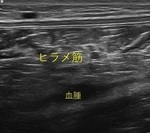

症例紹介